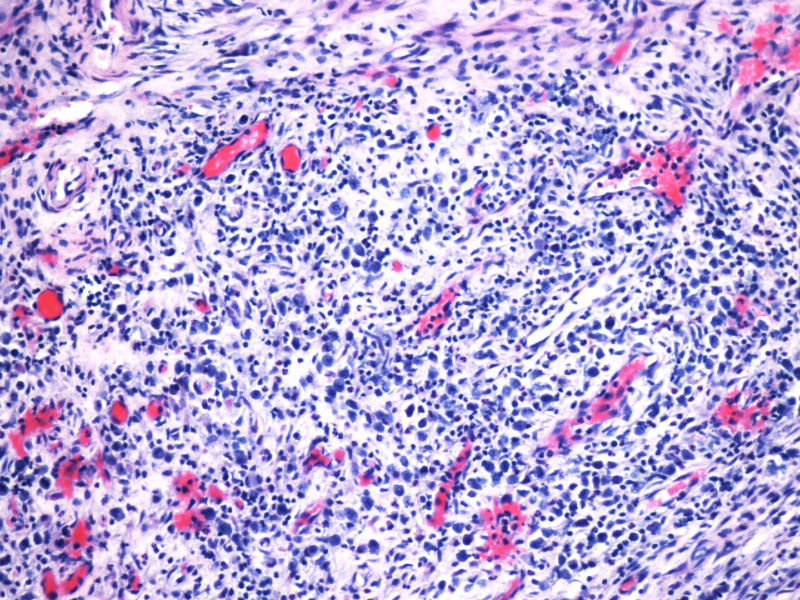

的确如此,CD43不仅表达于多量T细胞淋巴瘤,还可以表达于一些B细胞淋巴瘤,如套细胞淋巴瘤、小淋巴细胞淋巴瘤/白血病、粒细胞肉瘤等等,甚至还可以表达于一些非肿瘤细胞。本例CD2,CD3,CD4,CD8,CD5,CD7均阴性,在这样的大细胞病变形态基础上,此时做CD43和细胞毒标记物只是寻找诊断ALCL的佐证,后来果然CD43和部分细胞毒标志物是阳性,对于“裸”免疫表型的ALCL,这一诊断思路也是WHO和许多文献推荐的,日常工作中也是我们也常常是这样做的。如果病变是在淋巴结内,HE是大细胞病变,且出现上述免疫表型,我想应该有许多病理医生就诊断了ALCL了。只是本例部位等临床特征特殊,诊断需要慎之又慎,但最后ALK-1也显示大细胞阳性,就增加了诊断的信心。

本例全B,全T缺失,使诊断很困难,淋巴瘤范围内一般考虑①HL;②浆细胞分化的肿瘤如浆细胞骨髓瘤或浆母细胞瘤;③ALCL. 以下为鉴别:

形态学hallmark 细胞显示不是很清晰,大的肿瘤细胞如果在ALCL和HL之间选择可能不容易,但HL的肿瘤细胞形态学特点的范围比较狭窄,而ALCL可能具有更广泛的形态学范围,细胞大小形态以及典型hallmark cell的多少有时很难确定。如果只看HE,觉得ALCL的可能会安全一点,当然我个人经验不足,可能理解得比较肤浅。

此病例是非常特殊,其表现为:

1)ALCL很少原发于骨组织,

2)肿瘤细胞免疫表型特殊, CD30+CD15+ALK-1+CD43+Perforin+, 而其他PanB细胞和PanT细胞的标记均为阴性。

3)楼主诊断ALCL主要根据是 ALK-1+, 很有说服力!